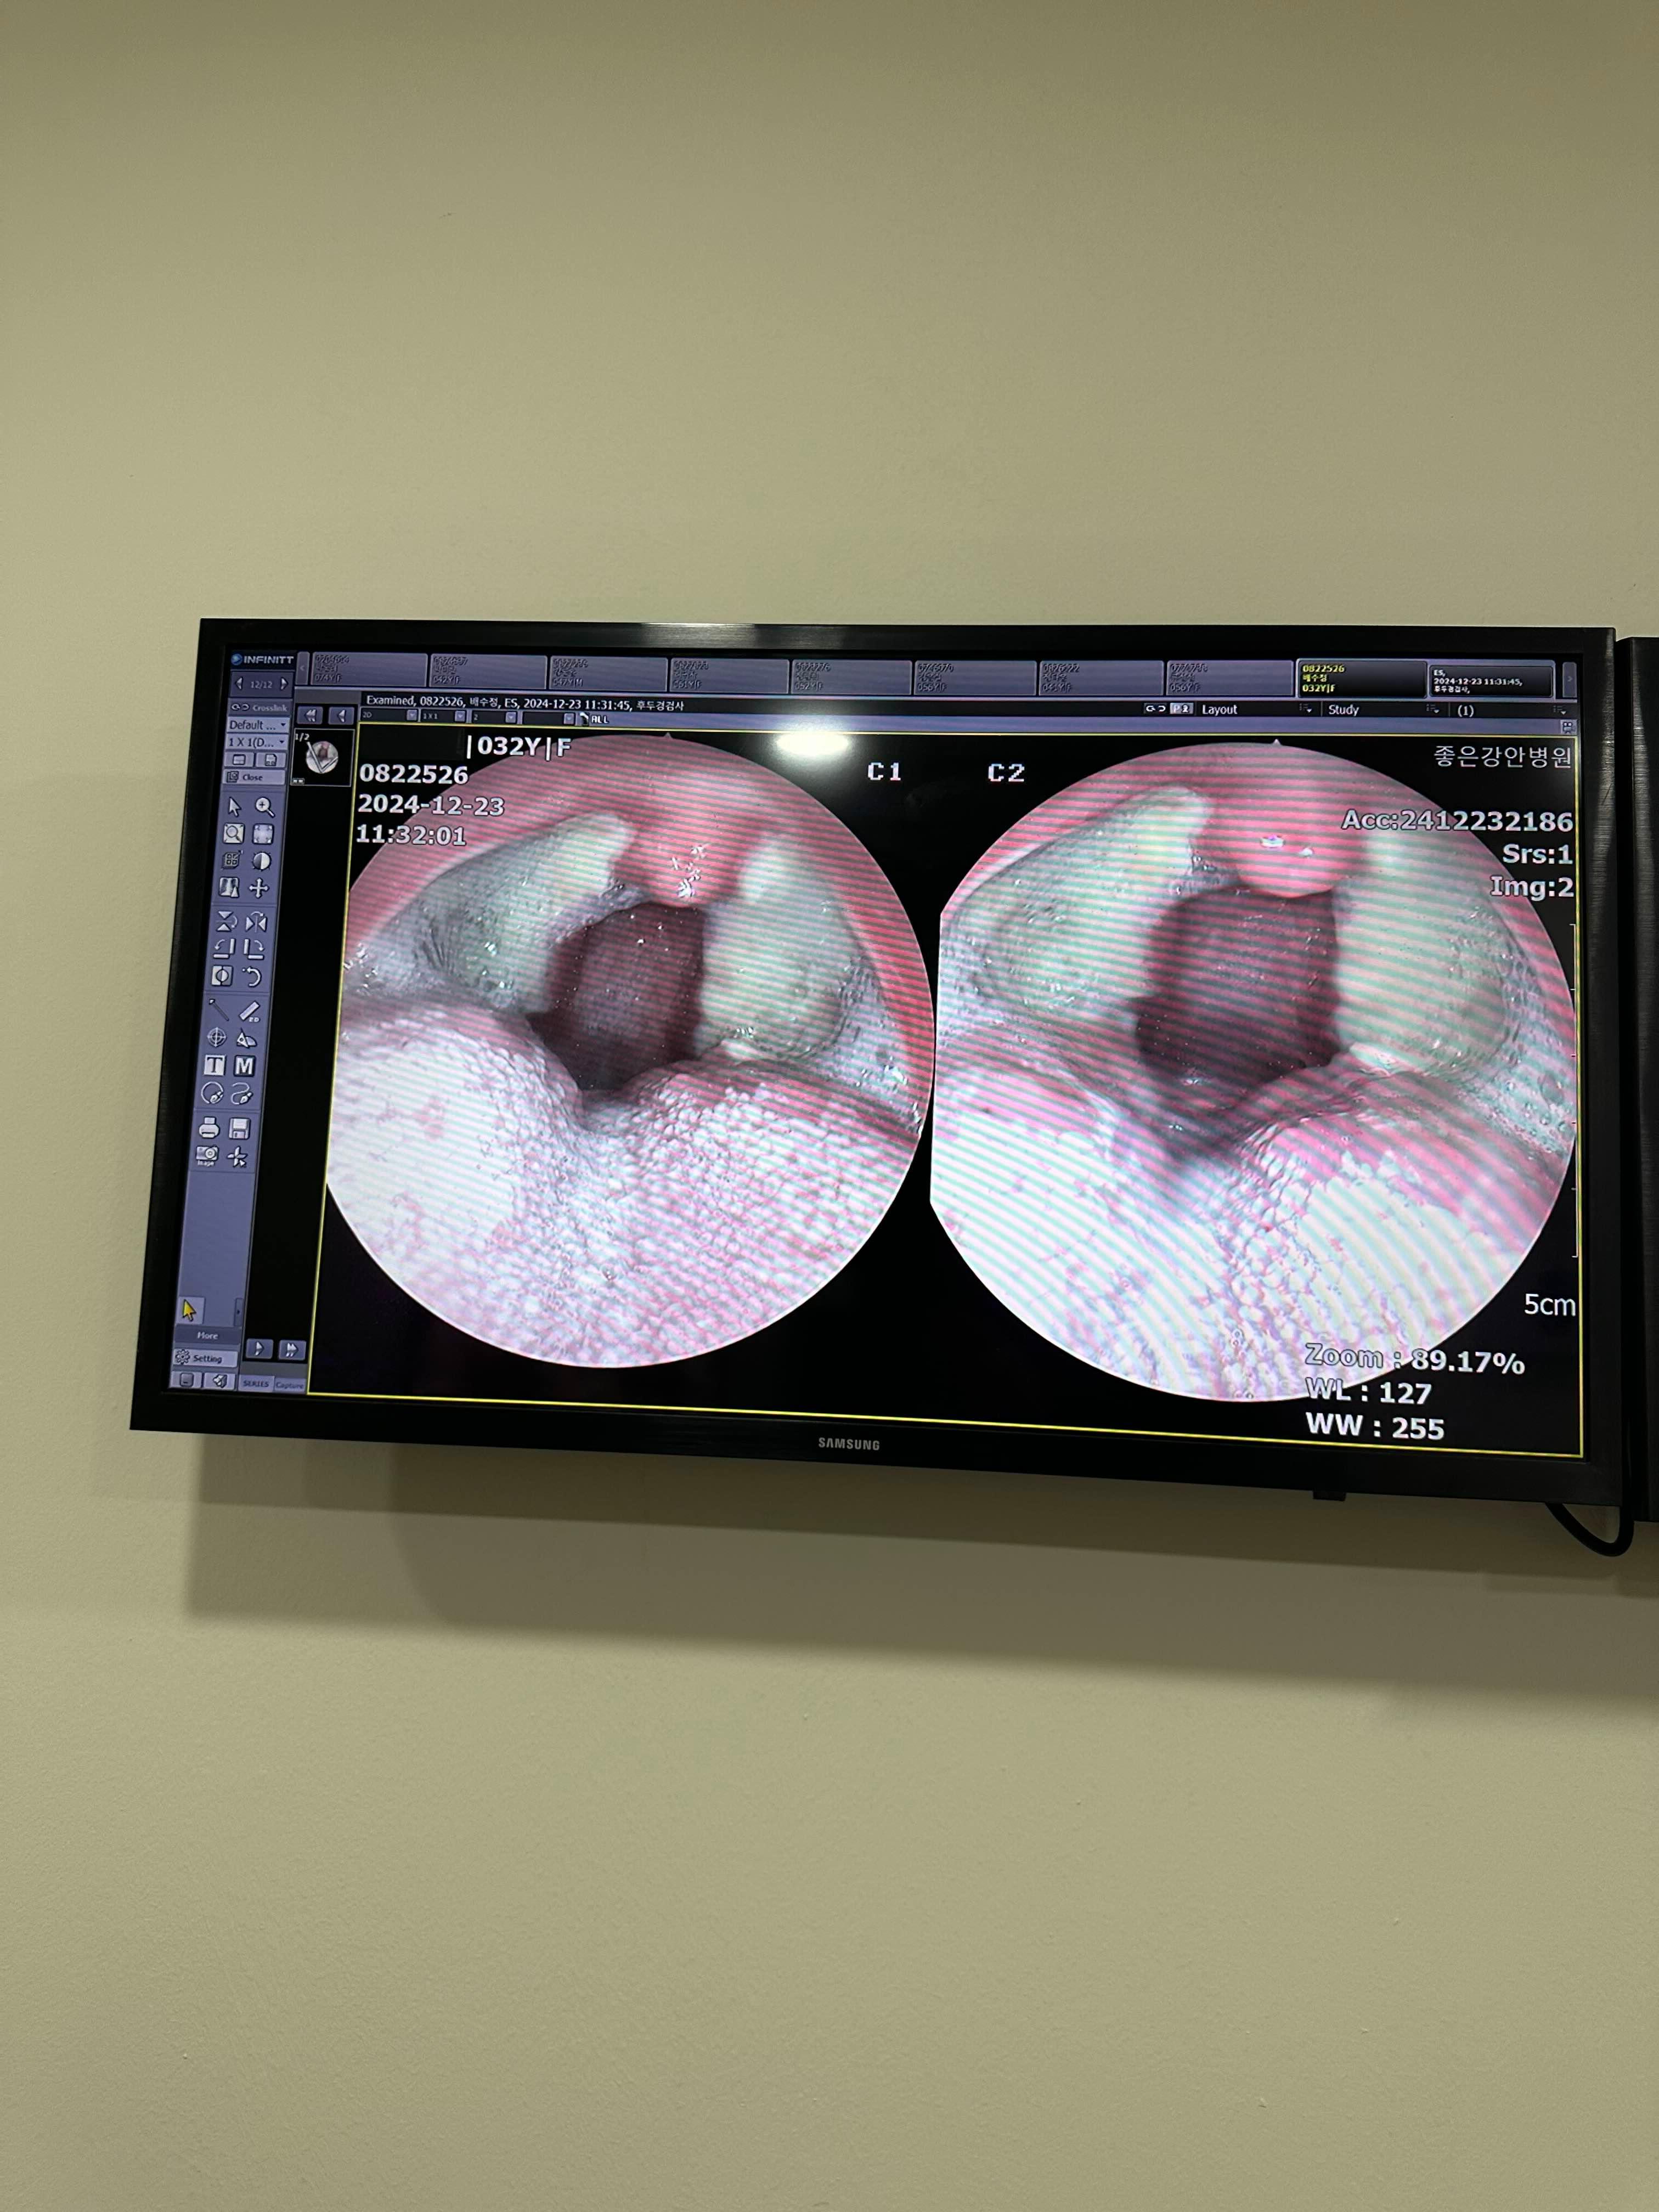

이게 수술후 2주 된 지금.

목이 갈수록 너무 좋아짐.

새살이 잘 차오르고 있다하시고~

먹는것도 이제는 좀더 편히 먹어도 된다는 말을들음.